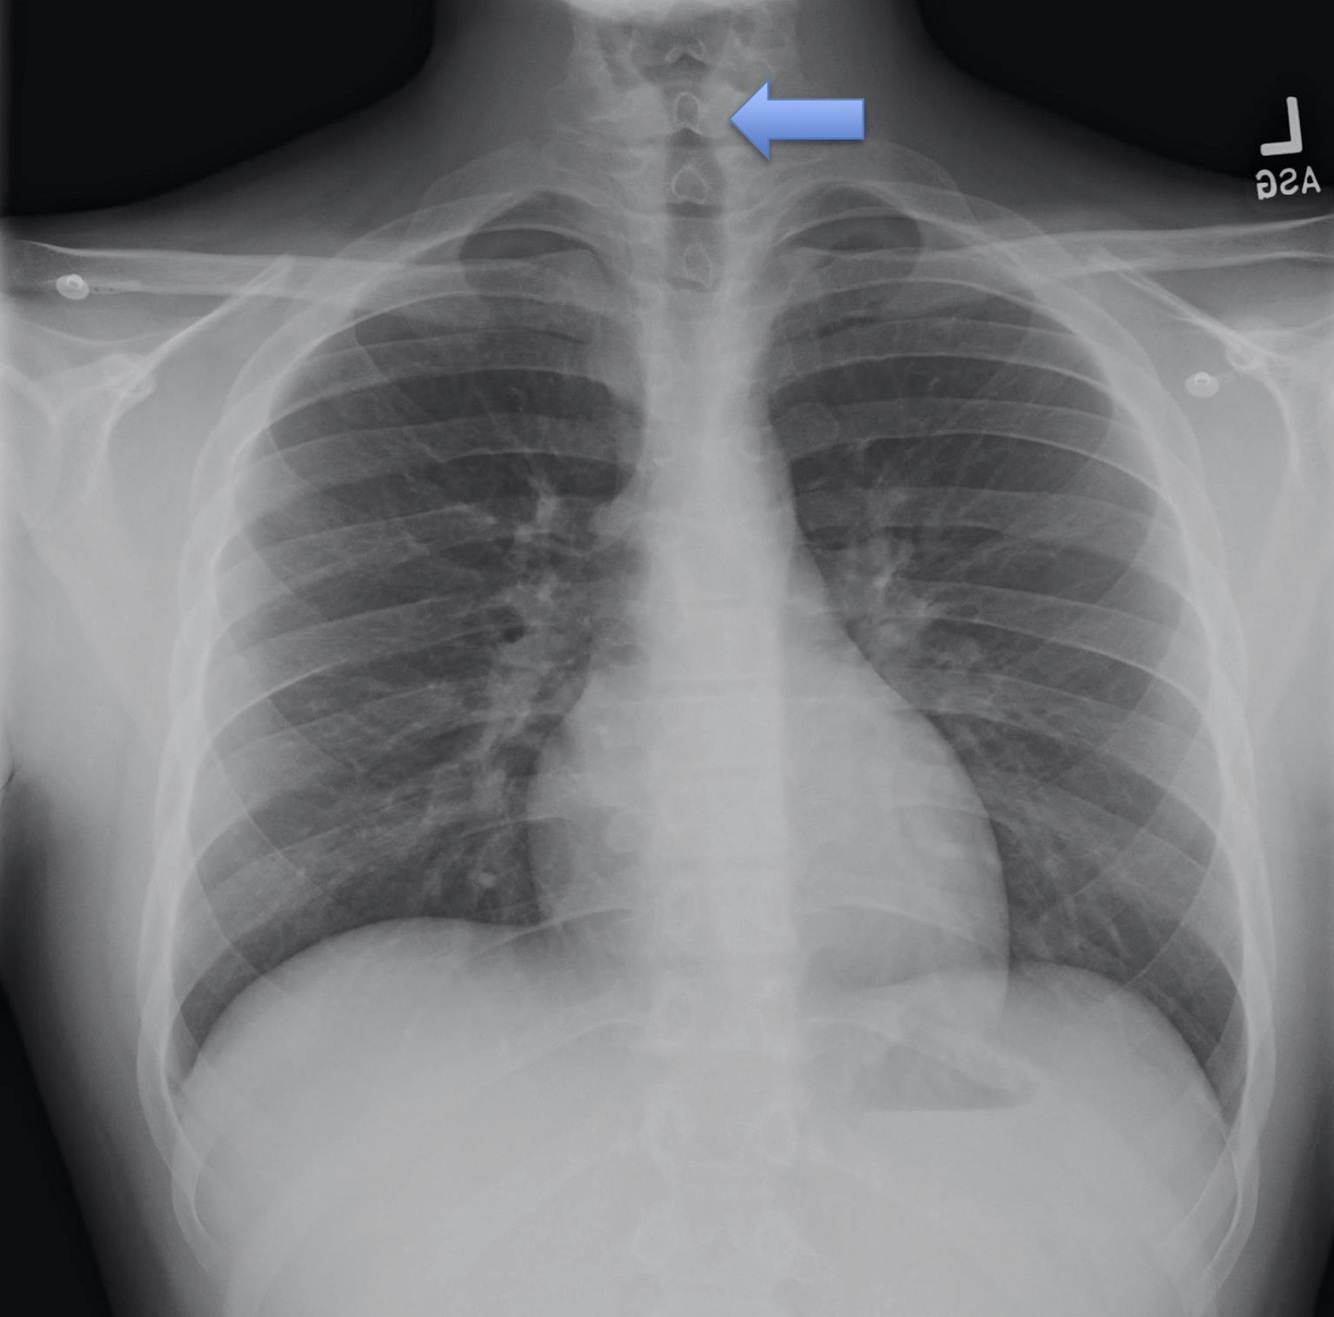

Trachea

Normally found in the midline.

Abnormalities:

Tube placement

Tension pneumothorax

Lateral View